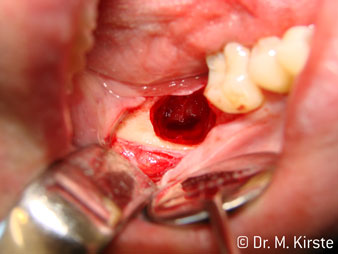

45° açılı angldruva geniş avantaj yelpazesi sebebiyle özellikle seçildi. Bu enstrümanın geliştirilme nedeni olan cerrah meslektaşlarım angldruvaların kısıtlı alanlardaki çalışma yeteneğini yakında takdir edeceklerdir. Özellikle gömük diş çekimlerinde (res. 2) yumuşak dokunun yanak bölgesine doğru yarılmasına gerek kalmaz(res. 3). Angldruvanın kafa dizaynı sayesinde retromolar bölgede hızlı ve güvenli çalışma sağlar.

Hızlı çalışmadan bahsetmişken: angldruva, 100,000 rpm üzerinde çalışırken aynı anda profesyonel bir soğutma sağlanır

Angldruva kafası içindeki profesyonel tasarımlı dişliler frezin sessiz çalışmasını garanti eder; kök separasyonu yapılırken atravmatik operasyona olanak verir. (res. 4-9).

45° açılı angldruva çok rahat kavranıyor. Angldruva çalışırken işaret parmağınızın açısını takit ettiğini görebilirsiniz, planladığınız işlemi kusursuz bir şekilde tamamlarsınız. (res. 1)”